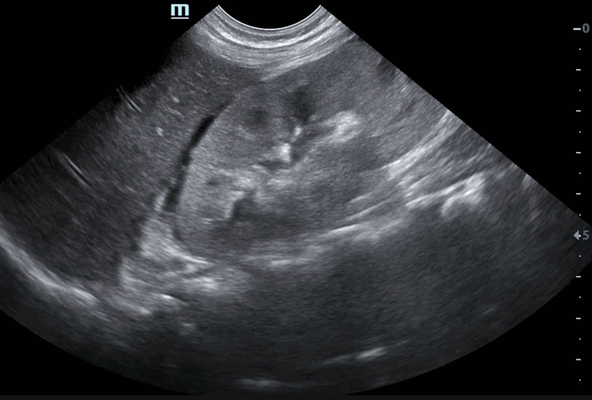

Ультразвуковое изображение расширения полостных систем обеих почек у плода

В норме ЧЛС анэхогенна и не визуализируется. Камни размером 4-5 мм и более в УЗИ-заключении описываются как эхотень, гиперэхогенное включение, эхогенное образование. Наличие песка обозначается как микрокалькулез почек.